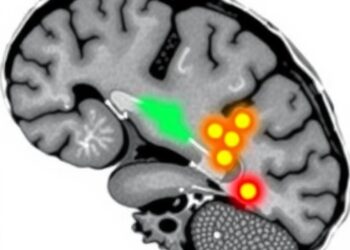

Investigating deeper into this connection, the researchers identified the basolateral amygdala (BLA) in the brain, which plays a pivotal role in processing emotions such as fear and anxiety. Their studies suggested that heightened activity in the BLA was closely linked to the absence of beneficial microbes. This phenomenon was attributable to calcium-dependent SK2 channels within brain cells, which are implicated in modulating anxiety-related behavior. Under normal conditions where the system is exposed to live microbial metabolites, these SK2 channels function effectively to prevent neurons from excessive excitation, stabilizing emotional responses.

The research team, led by Associate Professor Shawn Je, delved further into the impact of reintroducing live microbes into germ-free mice. The results were compelling: the introduction of microbial populations resulted in a substantial decrease in neuronal hyperactivity in the BLA. Consequently, these mice exhibited much lower levels of anxiety-related behavior, aligning their emotional responses with those of mice that had an established microbial community.

Additionally, the team explored the therapeutic potential of indoles, the specific metabolites produced by certain gut microbes. Germ-free mice that received indole treatment showed a marked reduction in BLA activity and exhibited less anxiety-related behavior. This crucial observation reinforces the hypothesis that our indigenous microbiota could significantly influence our emotional well-being through the production of beneficial metabolites.